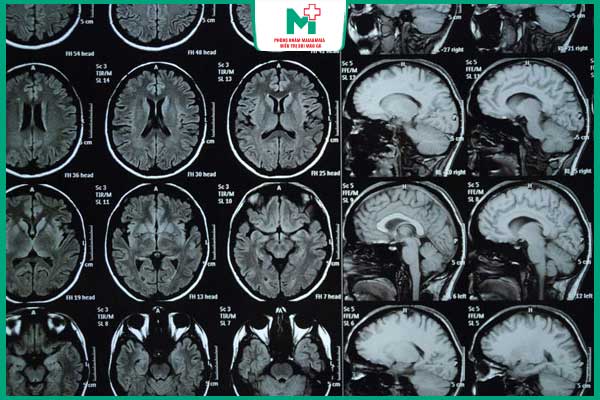

- Giang mai thần kinh: Là thể nặng nhất khi xoắn khuẩn xâm nhập vào hệ thần kinh trung ương, gây mất trí nhớ, rối loạn cảm giác, liệt chi, động kinh hoặc mù lòa. Một số trường hợp bị biến đổi tính cách, ảo giác hoặc sa sút trí tuệ.

- Chẩn đoán hình ảnh (MRI, CT, X-quang): Kiểm tra tổn thương tại não, tim, xương hoặc gan.